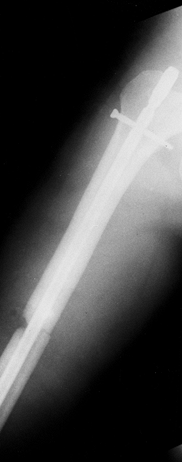

Closed transverse midshaft fracture of the right femur (Fig. 14.7). Figure 14.7. Midshaft fracture of the right femur. Figure 14.7. Midshaft fracture of the right femur.

decubitus position, and simultaneous surgery was carried out on the

right upper and right lower extremities. The humerus fracture was

internally fixed with an antegrade intramedullary nail utilizing closed

technique. The right femur was fixed with an intramedullary nail,

nonreamed, inserted antegrade, with a small exposure of the fracture

site to permit reduction and passage of the nail. Distal cross-locking

was not carried out (Fig. 14.12).

| Figure 14.12. Right femur after initial nailing. |